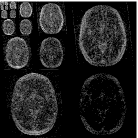

Baseline 5 months 10 months 20 months 23 months

While the scenario of longitudinal studies is fundamentally different from dynamic MRI in many aspects, we still find that similarity across time points exists in many cases. Figure 1 shows an example of the same axial slice taken from multiple scans acquired from a patient with Optic Pathway Glioma (OPG), demonstrating a relatively slow growing tumor pattern. The bottom row of the figure shows the representation of each time point in Daubechies-4 wavelet transform (Daubechies et al., 1992), which is widely used as a sparse transform for brain MRI. The similarity between image slices acquired at several time points is clearly demonstrated. Moreover, the representation of the images in the wavelet domain is sparse, and the locations of the dominant wavelet coefficients (a.k.a the support of the image in the wavelet domain) are similar across the patient’s time points.